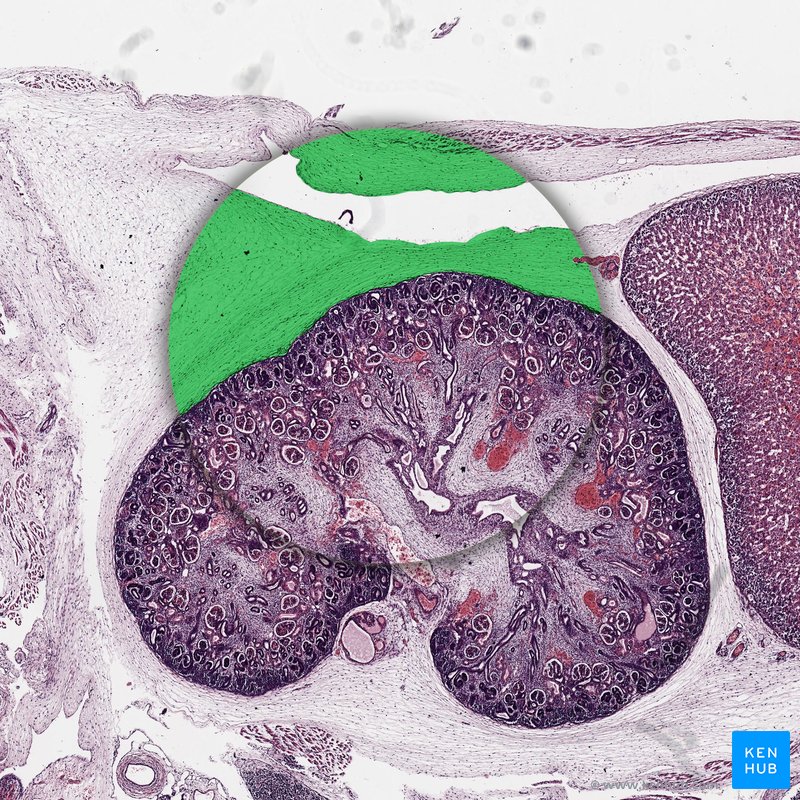

Tecido adiposo branco

Os adipócitos no tecido adiposo branco são organizados em lóbulos por septos de tecido conjuntivo. Os septos contêm fibras de colágeno, terminações nervosas, capilares sanguíneos e linfáticos. A matriz extracelular de tecido adiposo branco é feita de fibras reticulares e contém células não residentes do tecido adiposo (por exemplo, células inflamatórias).

Em uma lâmina histológica, os adipócitos aparecem vazios, com uma fina borda de citoplasma próximo à lâmina basal. Isso é descrito como a aparência de "anel de sinete" do tecido unilocular. Isso ocorre pois a gota de gordura intracelular se dissolve quando tingida com métodos de coloração histológicos padrão (coloração HE).